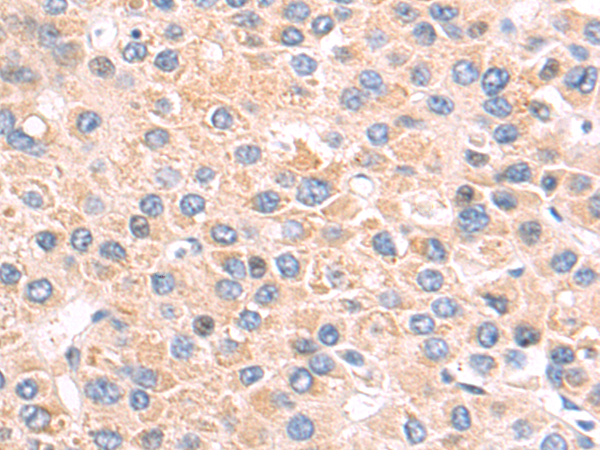

分类: 科研抗体货号: P04914别名: H963应用: WB,IHC反应种属: Human